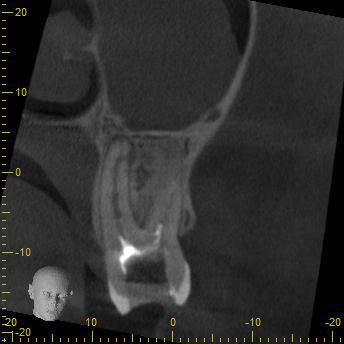

BN2627_DVT (1 von 17) Veröffentlicht 1. Dezember 2014 am 344 × 344 in Unerwartete Anatomie Zahn 26, 27- die WF